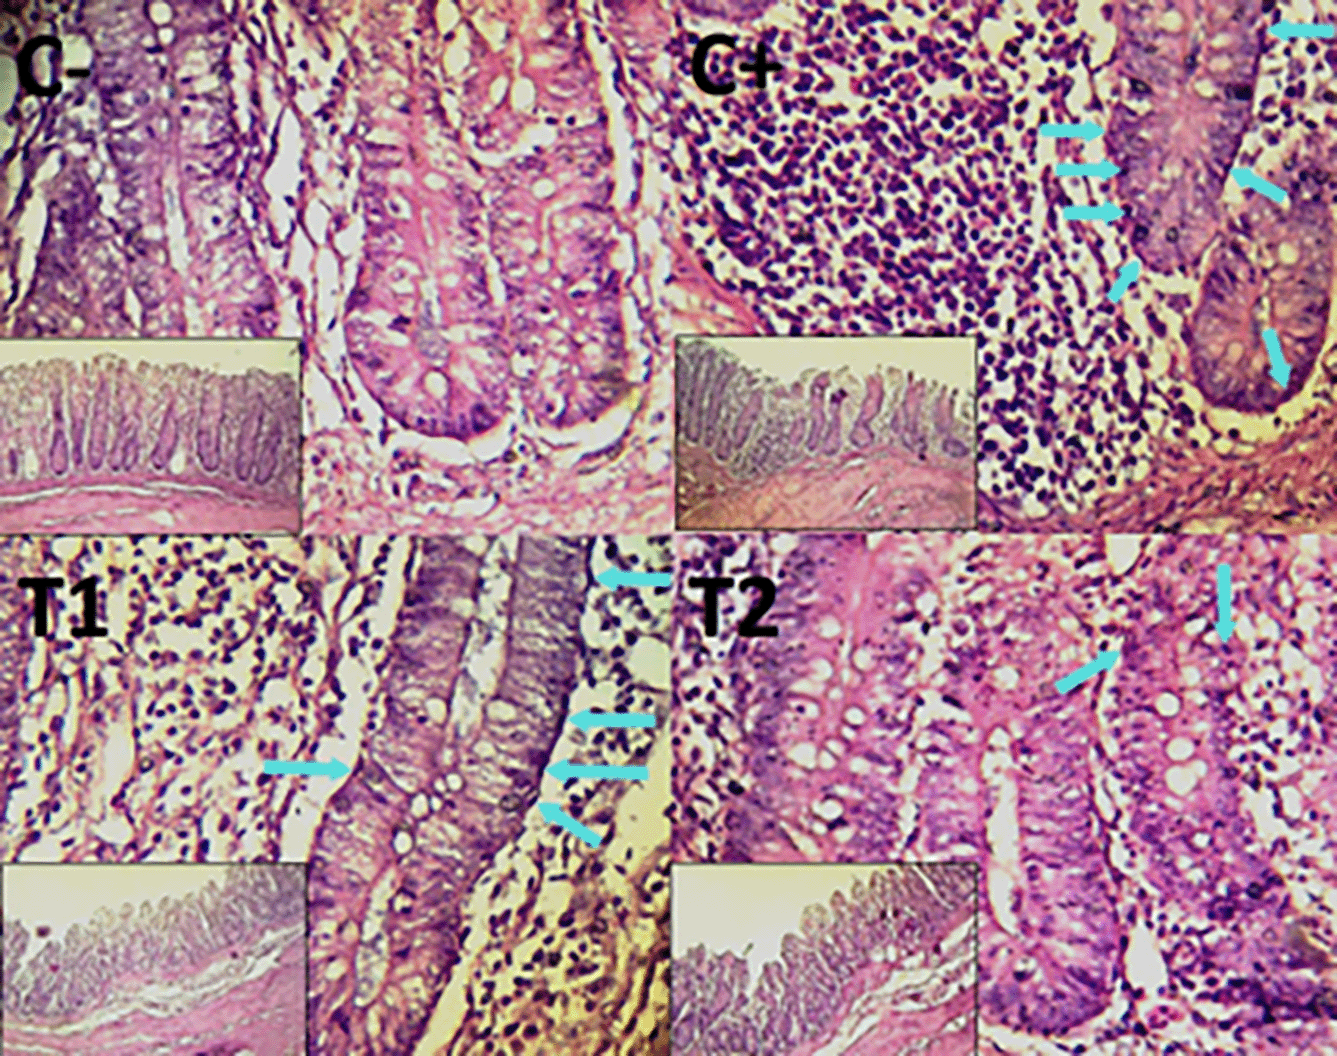

Histopathological improvement of the cecum and colon was reported based on reduced mucosal rupture, hemorrhage and necrosis on day 35.

The findings of the scoring analysis of the broiler chickens’ mucosal rupture, necrosis, and hemorrhage in the cecum ( Table 2) and colon ( Table 3). The control group (C-), had the lowest mean rank. The C+ treatment group, had the highest mean rank. The T1 treatment group and Treatment group T2 as indicated in Table 2. Furthermore, the T2 group demonstrated a progressive improvement in the histological differences related to mucosal rupture, hemorrhage, and necrosis in the cecum organ ( Figures 2–4).

The control group, treatment group C-, had the lowest mean rank. Treatment group C+, had the highest mean rank. The T1 treatment group. Table 3 shows that the T2 treatment group demonstrated a progressive improvement in the histological differences of mucosal rupture, haemorrhage, and necrosis in the colon organ ( Figures 5–7).